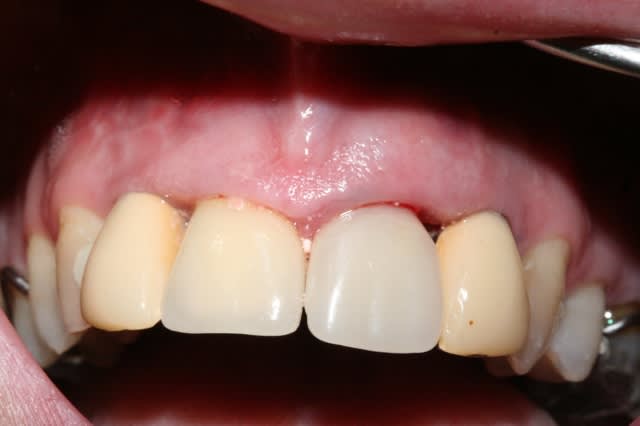

fracture d'une racine 21, infection vestibulaire

1 vue clinique

2 provisoire réalisée avec empreinte de la patiente en ayant retiré la couronne (histoire d'avoir la forme exacte de la gencive le jour de l'extraction)

3 et 4 fendu = foutu !

5 oups ... même photo.

6 RTR en place mais extraction du pan vestibulaire seulement pour avoir un site non infecté et une gencive cicatrisée (donc plus facile à suturée)le jour de la pose de l'implant.

7 dent provisoire maintenant la gencive en place.

ma question;

auriez vous extrait la dent dans sa totalité tout de suite en implantant immédiatement avec les risques infectieux? ou alors extraction, cicatrisation (et donc perte du volume gingivale) puis implantation?